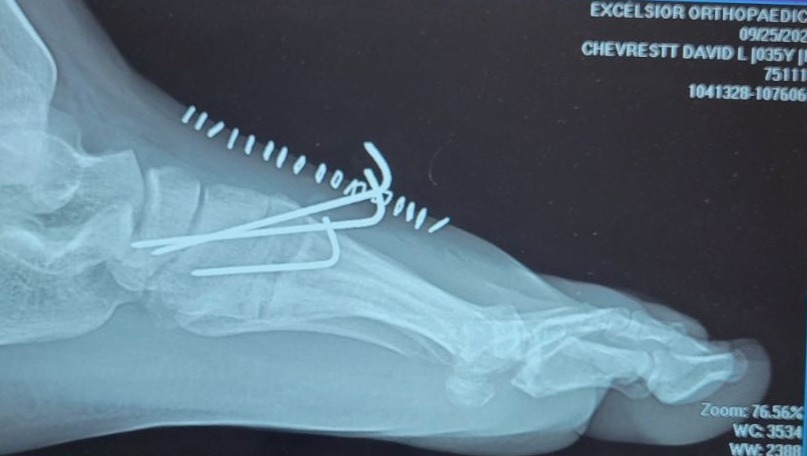

While playing in a Not Very Important game of recreational softball - stone-cold sober of all things - our friend David (Dave if you're an O.G.) managed to fracture 3 bones in his mid-foot sliding into home plate.